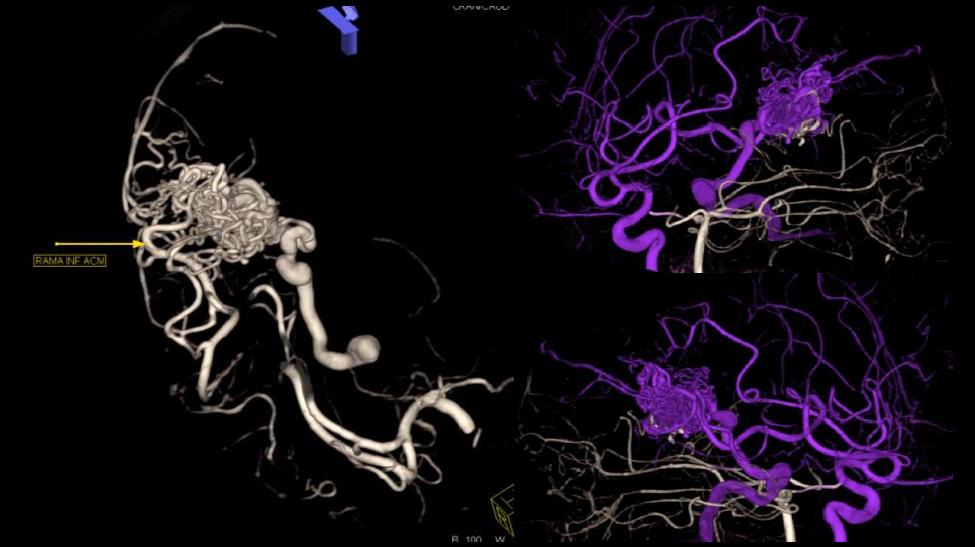

Tratamiento combinado de malformación arteriovenosa con sangrado reciente